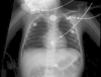

Presentamos el caso de un paciente varón de 23 meses previamente sano, enviado desde un hospital comarcal con los diagnósticos de cuerpo extraño esofágico y hematemesis con shock hemorrágico secundario. Los padres referían un cuadro de odinofagia, sialorrea y estridor de 2 semanas de evolución sin mejoría tras tratamiento con corticoides y sin antecedentes de ingesta de cuerpo extraño. A su llegada a nuestro hospital se encontraba hemodinámicamente estable. Se realizó analítica, que fue normal, y radiografía de tórax donde se confirma la existencia del cuerpo extraño radioopaco, redondeado en tercio superior del esófago (fig. 1). Es valorado por cirugía pediátrica y endoscopistas decidiéndose la extracción urgente endoscópica en quirófano, realizada a los 45 min de su ingreso en nuestro centro. En la endoscopia se visualiza el cuerpo extraño que en el intento de extracción se desplaza accidentalmente al estómago, quedando una úlcera con restos hemáticos, sin sangrado activo en ese momento. Se decide no extraer el objeto por la elevada posibilidad de perforación de la zona ulcerada. El niño es trasladado a la UCI pediátrica habiendo presentado hematemesis repetidas tanto a su entrada a quirófano como a su llegada a la UCI. Se constata la situación de shock hemorrágico iniciándose fármacos vasoactivos y hemoderivados. A los 45 min de ingreso y a las 4 h presenta 2 episodios de PCR que remontan tras RCP. Ante la imposibilidad de trasladar al paciente a quirófano por la inestabilidad hemodinámica que presentaba, se realizan 2 endoscopias visualizando un punto sangrante en la zona ulcerada. Se intenta la cauterización del mismo, así como la colocación de una sonda de Sengstaken, siendo ambas maniobras inefectivas. A las 7 h de ingreso presenta una nueva PCR que no remonta a pesar de RCP y fallece. La necropsia informa de fístula aortoesofágica en tercio superior del esófago.